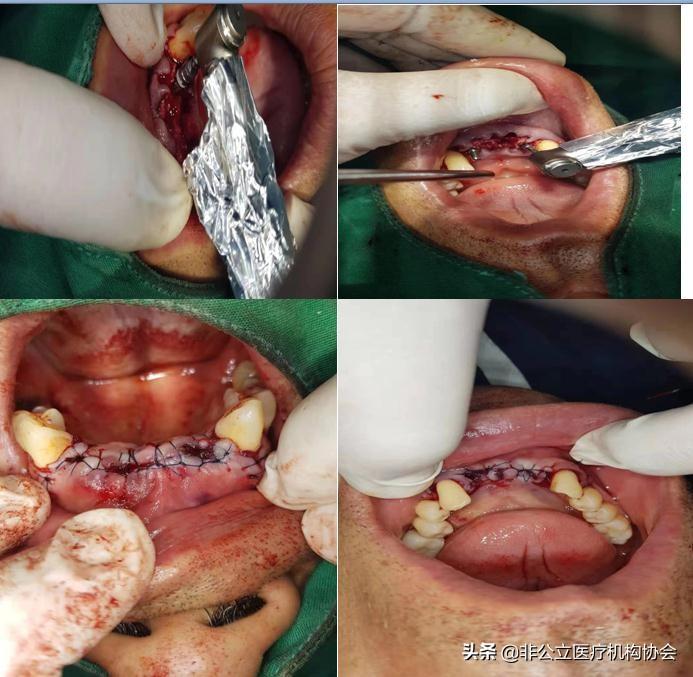

術(shù)前消毒(二)

患者術(shù)前的唇頰側(cè)觀(三)

患者術(shù)前病人的先拔牙(四)

新技術(shù)離心機(jī)抽血形成骨粉作用。

人工種植牙過(guò)程,很簡(jiǎn)單,就要拔除牙齒一樣的。